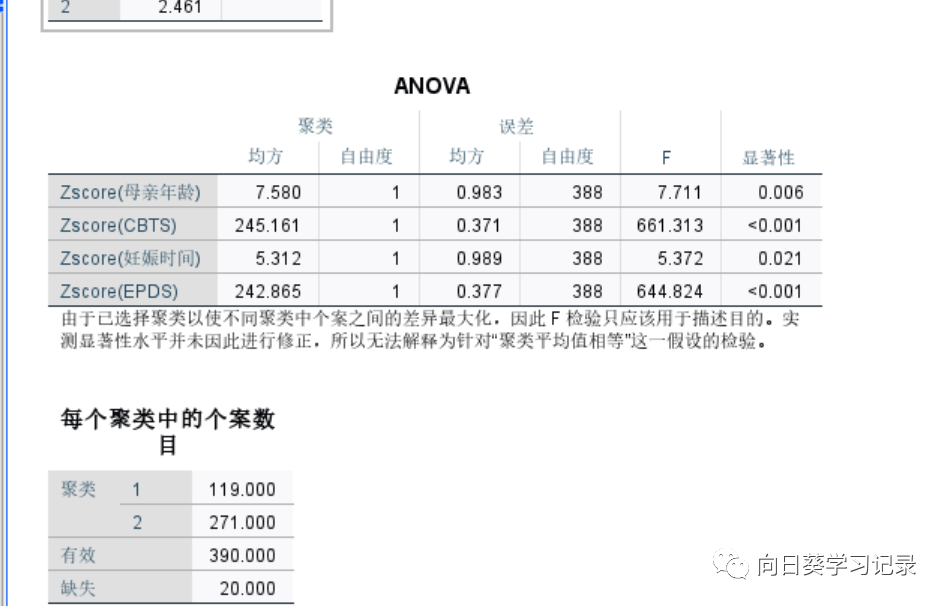

最后是给出了每个聚类的个案数和ANOVA检验,ANOVA表示每个变量在不同类别之间是否存在显著差异,若存在的越多则表明聚类效果越好,根据图中可知,CBTS和EPDS对聚类有贡献,且EPDS的F值最大,说明EPDS对聚类的影响最大,CBTS次之,妊娠时间最小。1类为119 2类为271

最后结果会输出为QCL_1,最后是对聚类后的结果进行描述(使用之前的变量),来说明每个类别的含义